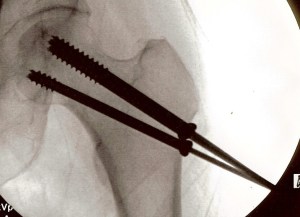

Unfortunately, that wasn’t the case; I had fractured my hip and was transported to the hospital for surgery to put it all back together again.

I’ll spare you the details, but I now have three pins installed in my left hip. If all goes well—and there is no reason it shouldn’t—these pins will be a permanent part of my anatomy. They will allow the bones to heal correctly then live on to become the reason I can never go through regular airport screening again. They will be some of the most expensive metal bling I own, yet no one can see them.